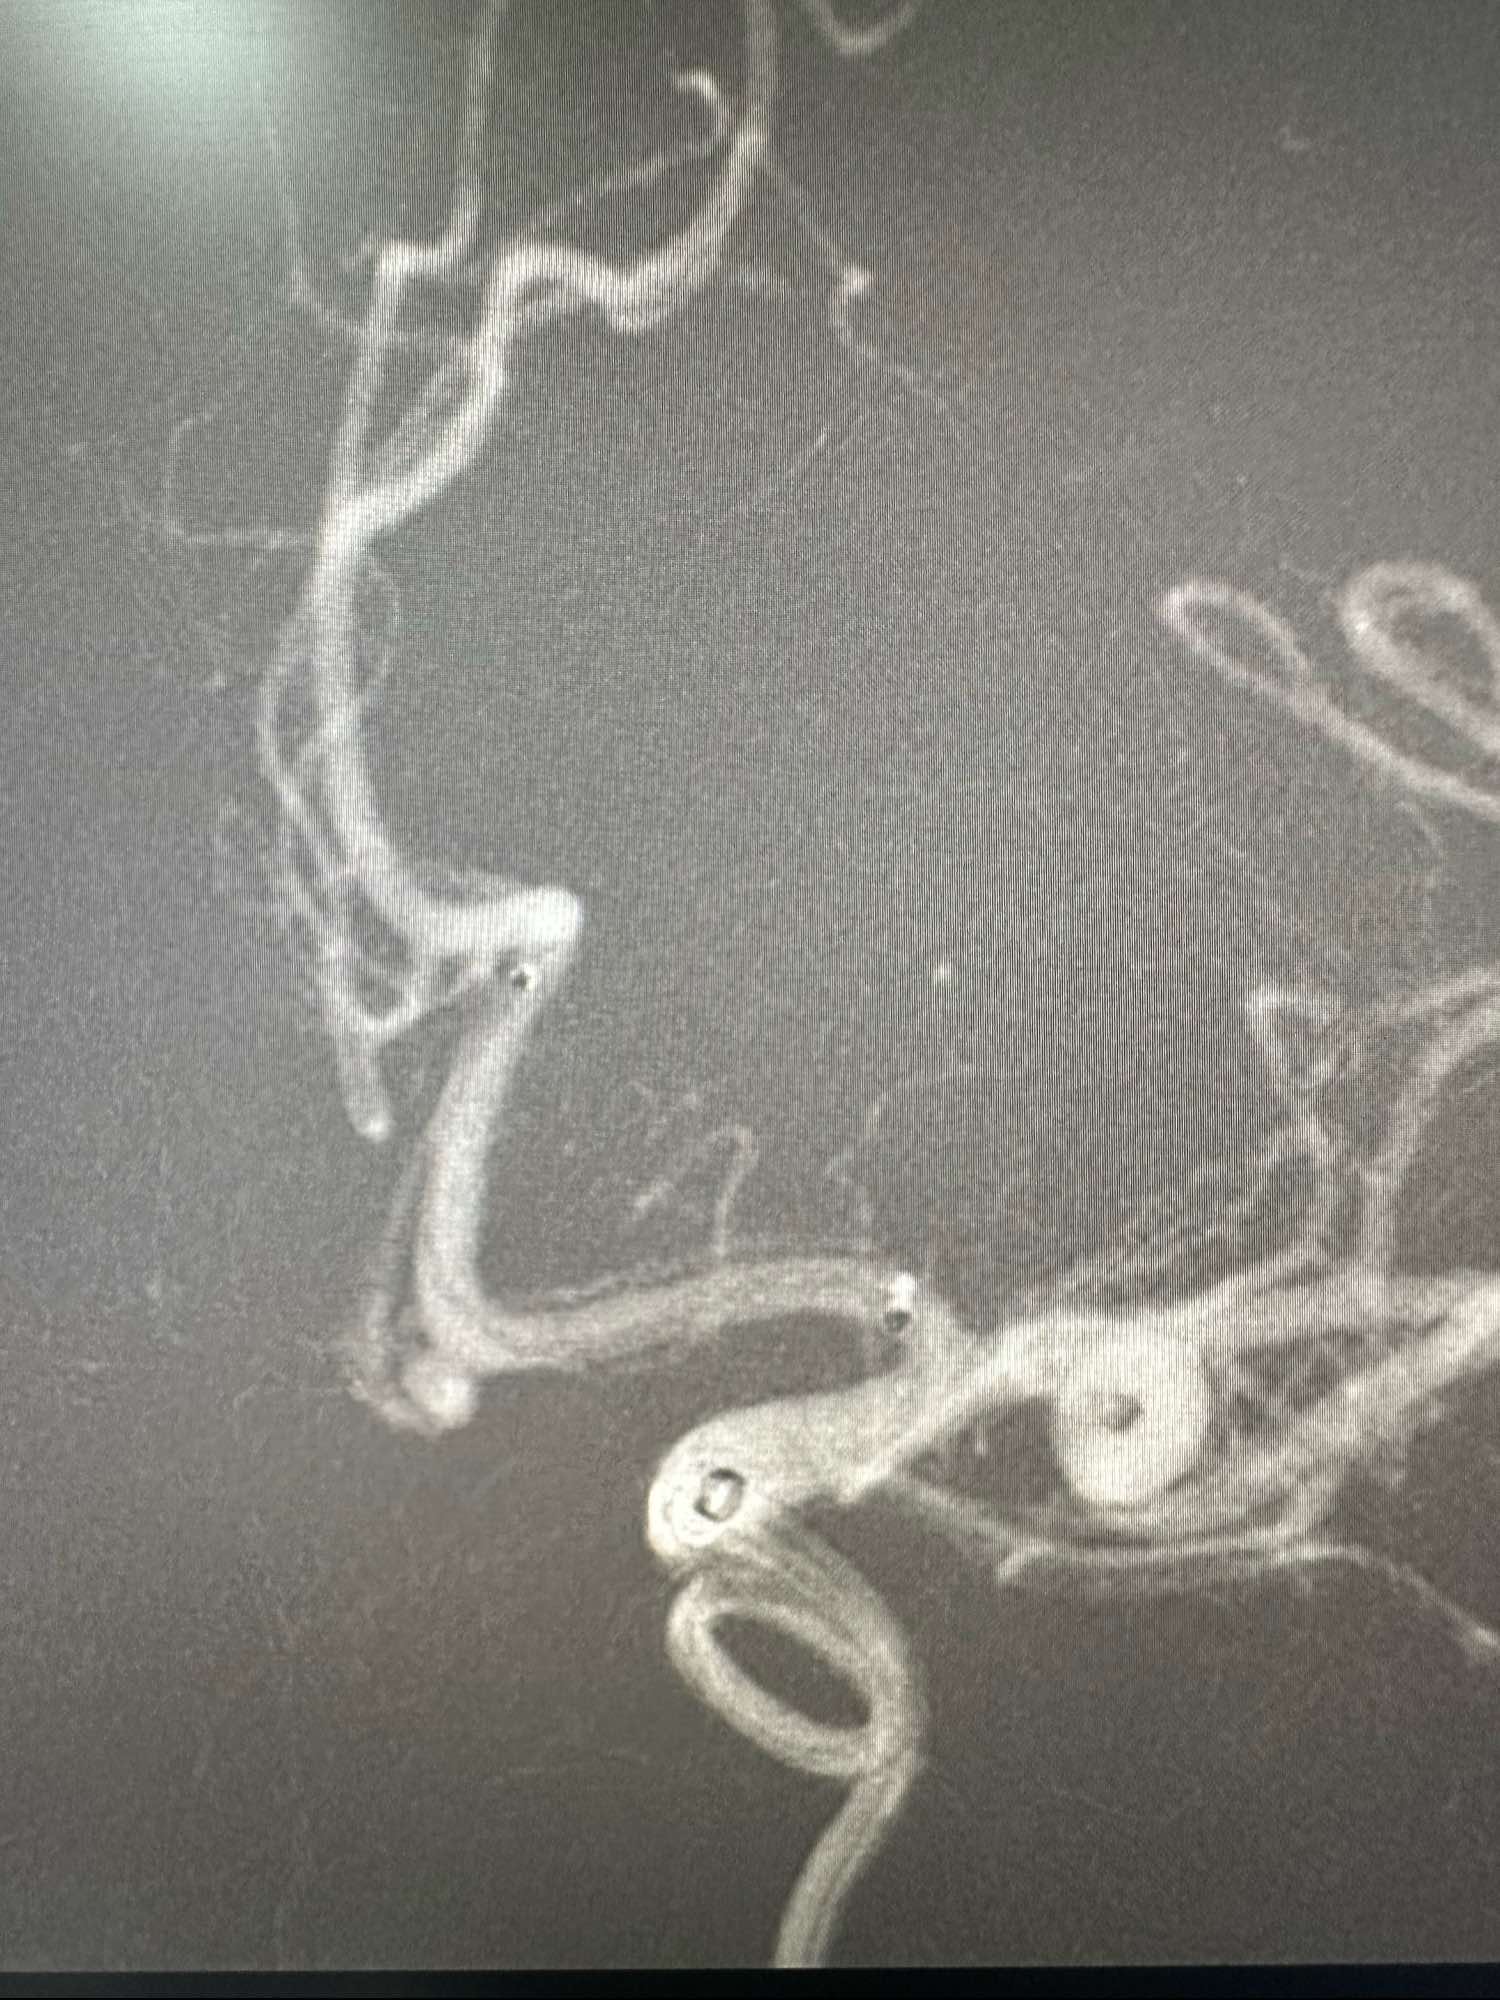

左侧颈内动脉造影3D